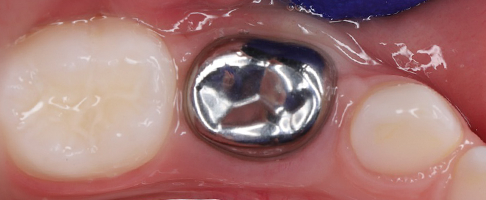

- восстановление молочных жевательных зубов коронками.

В работе доктор применяет современные биосовместимые материалы, а также изоляционную систему коффердам. Ведет фотопротокол для контроля качества работы и наблюдения результатов лечения в динамике.